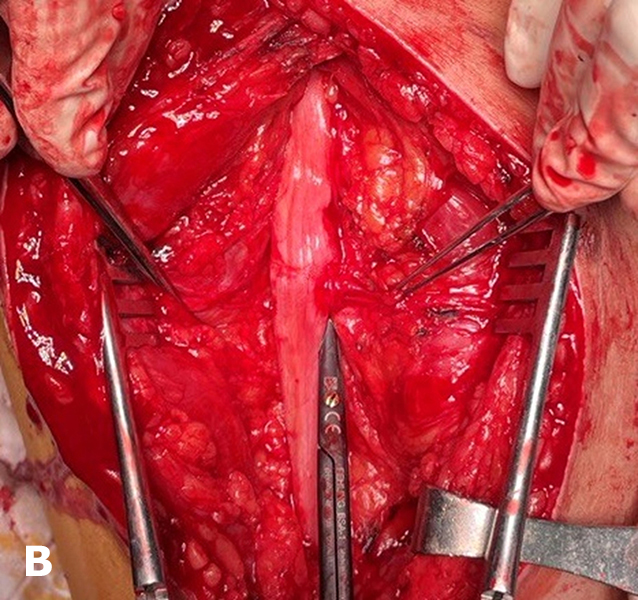

In patients with pain syndrome resulting from the formation of painful neuromas, the following surgical procedures were performed: neuroma resection with transposition of the nerve into deeper tissues (21.4% of cases); regenerative peripheral nerve interface (RPNI) creation (60.7%)—wrapping groups of fascicles of a mixed nerve with small fragments of denervated free skeletal muscle (Fig. 4); and targeted muscle reinnervation (TMR) (17.9%)—coaptation of the mixed nerve forming the painful neuroma to a motor nerve innervating the skeletal muscle of the residual limb (Fig. 5).

Fig. 4. Formation of a regenerative peripheral nerve interface (RPNI)